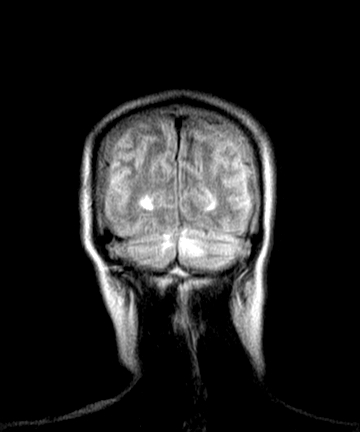

标题: MRI2064:少见病例。男性52,视力下降多年。 [打印本页]

标题: MRI2064:少见病例。男性52,视力下降多年。

四脑室区见混杂信号占位影,脑室系统扩张明显,临近结构显著受压称位,患者52岁,多考虑室管膜瘤可能性大

考虑第四脑室室管膜瘤并阻塞性脑积水。

考虑第四脑室室管膜瘤并梗阻性脑积水;部分性空蝶鞍;左侧上颌窦粘膜下囊肿。

考虑第四脑室室管膜瘤【血供丰富血管母细胞瘤可能】并梗阻性脑积水;部分性空蝶鞍;左侧上颌窦粘膜下囊肿。

比较典型的脉络丛乳头状瘤并脑积水,鉴别小脑蚓部血管母细胞瘤。